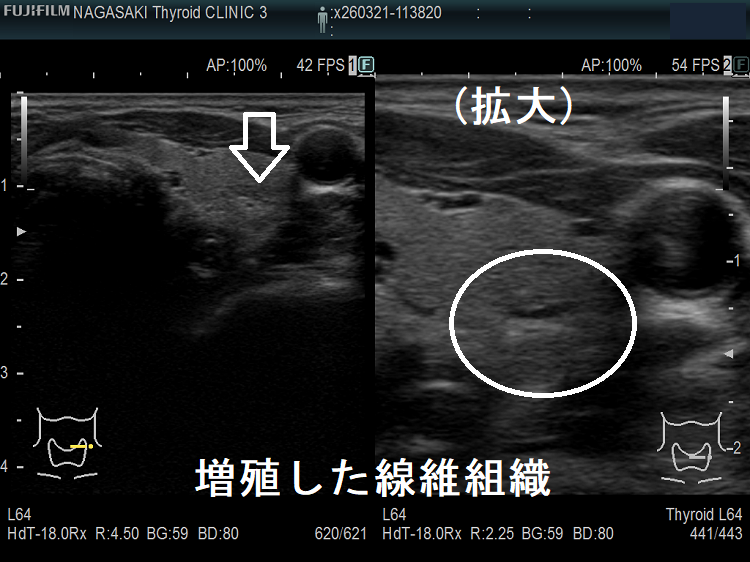

- 甲状腺癌と紛らわしい結節性橋本病(橋本病結節)